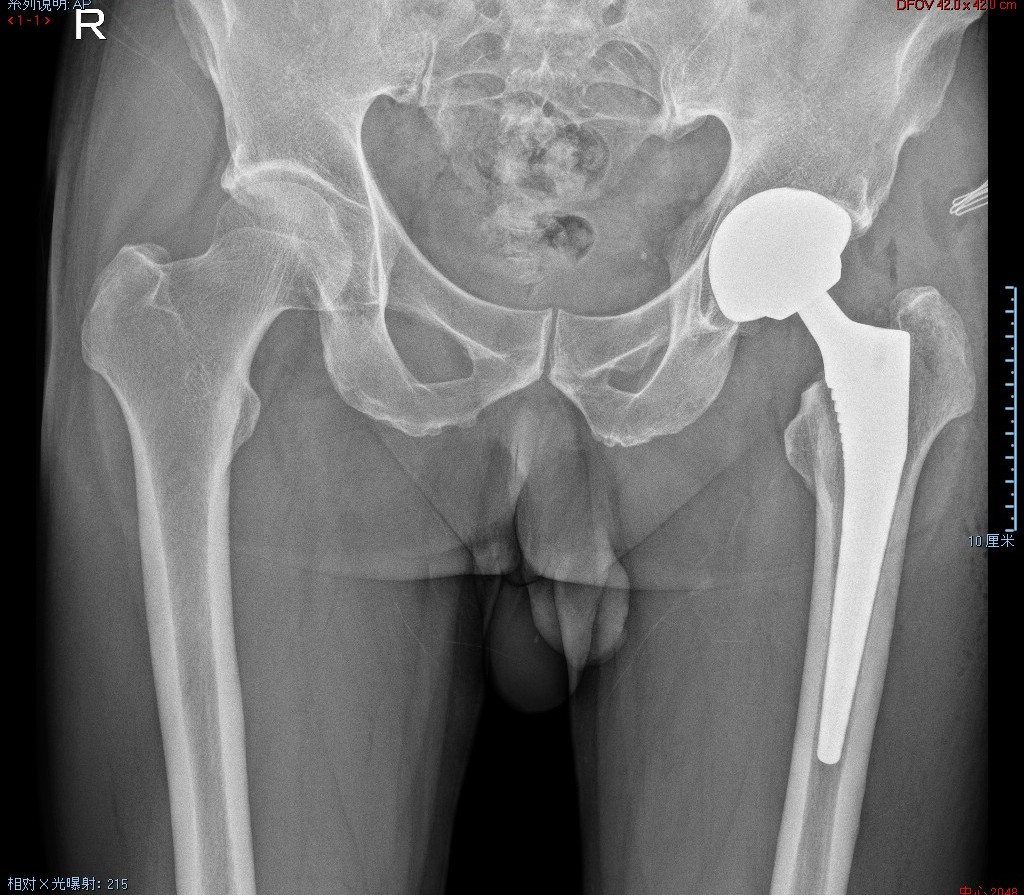

8月28日,关节外科一病区团队,成功开展了比基尼通道入路(AnteriorPATH®)微创全髋关节置换术,给髋关节疾病患者带来了新希望。

李先生(化名)今年55岁,因摔伤至左侧股骨颈骨折(头下型)。该类型骨折愈合能力差、股骨头坏死发生率高,陆鸣副主任医师团队综合考虑病情后,决定采用比基尼通道入路为患者实施微创全髋关节置换术。

手术完成后,李先生手术区域几乎没有疼痛感,术后4个小时就可以在助行器的帮助下负重行走。AnteriorPath®--(Anterior Percutanously Assisted Total Hip)比基尼入路通道辅助全髋关节置换术,是一种使用辅助通道的比基尼切口前入路髋关节置换手术。

该技术使用一个套筒作为通道直接抵达髋臼,从而实现直视下的髋臼侧相关操作,完全的肌间隙入路,术后可实现病人早期下床功能锻炼,减少手术并发症,缩短康复时间,属于微创中的微创,同时比基尼切口可减少损伤股外侧皮神经(LFCN)的几率、减少术后大腿前方皮肤麻木,而且切口走向隐蔽,术后基本不遗留疤痕。同时简化股骨侧操作,利于股骨柄的插入、减少潜在假体周围骨折发生、临床数据显示,相较于传统术式,该技术手术时间平均缩短30%,术中出血量也明显下降,不仅有限减轻了患者身体负担,也大大提高了手术的安全性及成功率。这一技术的成功应用,不仅是我院关节外科微创领域的重大突破,也为广大患者带来了更好的治疗选择。